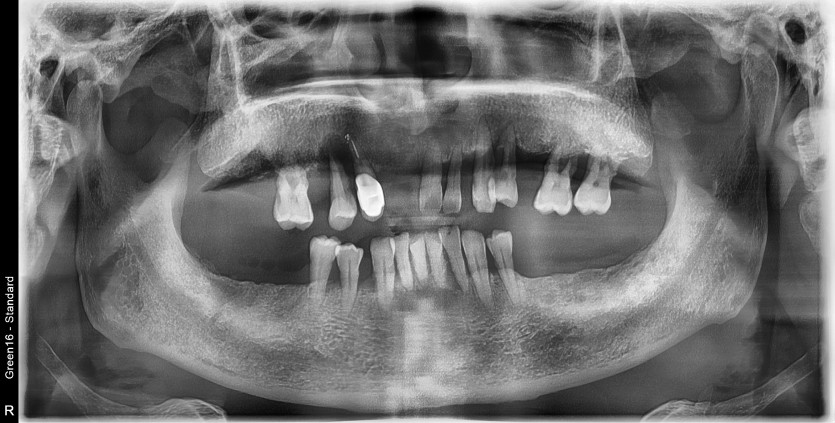

만 57세 풀아치 증례

풀아치 증례입니다.

6개의 임플란트로 완성하였습니다.